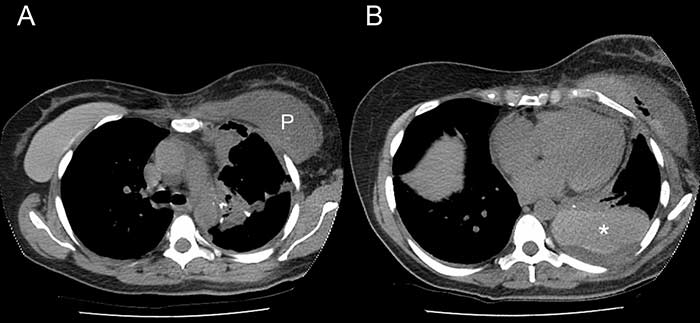

A. CT thorax showing the right implant in situ and the left implant capsule filled with pleural fluid (P).

B. The hyperdense left implant in the posterior pleural space (*) was misreported as hemothorax.

She returned to the emergency department twelve days later with pleuritic chest pain, nausea, and a low grade fever. A CT scan of the chest showed a high-density pleural effusion consistent with hemothorax. Since the patient was hemodynamically stable with no significant change in hemoglobin level, a pleural catheter was placed as the initial management. However, the effusion failed to resolve and further review of the imaging revealed that the left breast implant was no longer in the subpectoral position. What had been reported as blood in the pleural cavity was in fact the implant itself (Figure 1). The patient was brought to the operating room that day for VATS extraction of the implant and drainage of the pleural space. A Jackson-Pratt drain was inserted in the left breast implant capsule. She developed left mastitis post-operatively which was successfully treated with antibiotics and she was discharged five days later with follow-up with both thoracic surgery and plastic surgery.